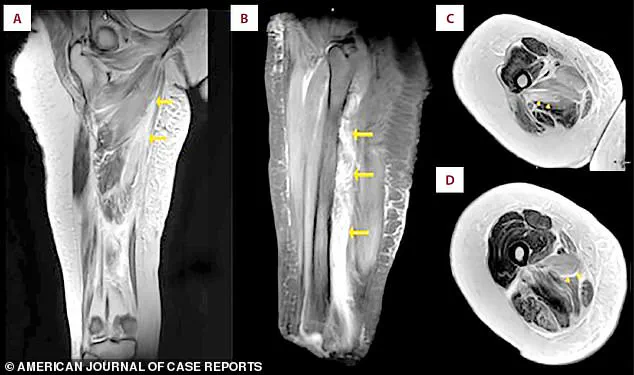

An MRI scan of the patient’s right thigh revealed widespread muscle swelling.

The images, marked with arrows, pinpointed this fluid buildup in the inner thigh muscles (the adductor group) and, in a different view, showed similar swelling affecting the muscles at the back of the thigh.

The MRI provided a detailed anatomical map of the damage, revealing the extent of the swelling and the specific muscle groups affected.

The fluid accumulation was a clear indicator of the inflammatory response and the breakdown of muscle tissue, offering valuable insights into the patient’s condition and guiding further treatment decisions.